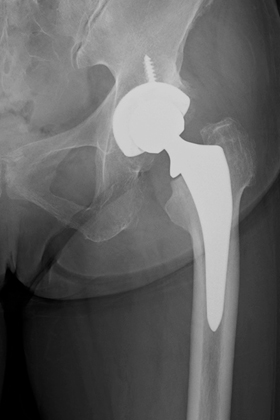

![]() 術後レントゲン |

人工股関節置換術とは、傷んで変形した関節を人工の関節に置き換える手術です。人工関節の表面は滑らかで神経もないため、この手術を受けることによって、関節は滑らかに動くようになり、痛みもほとんど感じなくなります。痛みなく歩けるようになると、日常生活を送りやすくなり、生活の質(QOL)を改善することができます。

手術では、まず変形した大腿骨頭を根元から切除し、傷んだ寛骨臼の表面の骨を削って取り除きます。寛骨臼側には金属のカップを骨に固定し、そのカップの内側に超高分子量ポリエチレン製の人工の軟骨(ライナー)をはめ込みます。大腿骨側には杭状の金属(ステム)を骨の中に挿入し、その先にセラミック製の人工の骨頭(ヘッド)を設置します。人工股関節はライナーとヘッドの間で滑らかに動く構造になっています。

人工股関節を骨に固定する方法には、「骨セメントを使用しない方法(セメントレス固定)」と「骨セメントを使用する方法(セメント固定)」の2種類があります。当院では、患者さんの年齢、骨の質、変形の程度などによって最適な方法を選択しています。